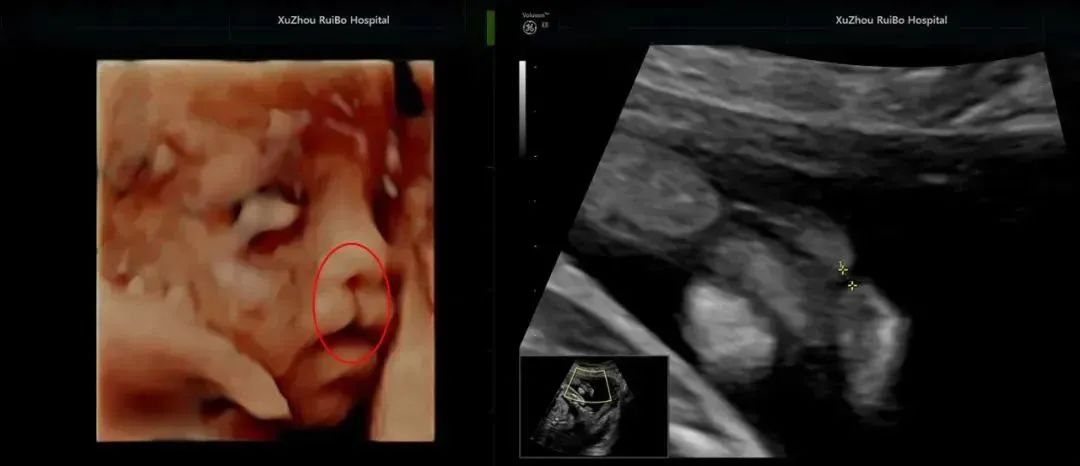

痛心!

两例四维彩超异常案例敲响警钟

胎儿面部发育异常——唇裂

△胎儿唇裂实机拍摄△

瑞博医院引进的美国GE-E8高清和GE-E10超高清超声设备,超越了传统超声的限制,通过细致的多切面成像分析胎儿的解剖结构及发育状况,检查范围更广、成像更清晰、筛查更精准、评估更科学、诊断更全面。清晰观察胎儿生长发育情况,完整获取临床超声诊断医学信息,为围产医生诊断胎儿发育情况提供更为准确的监测数据。